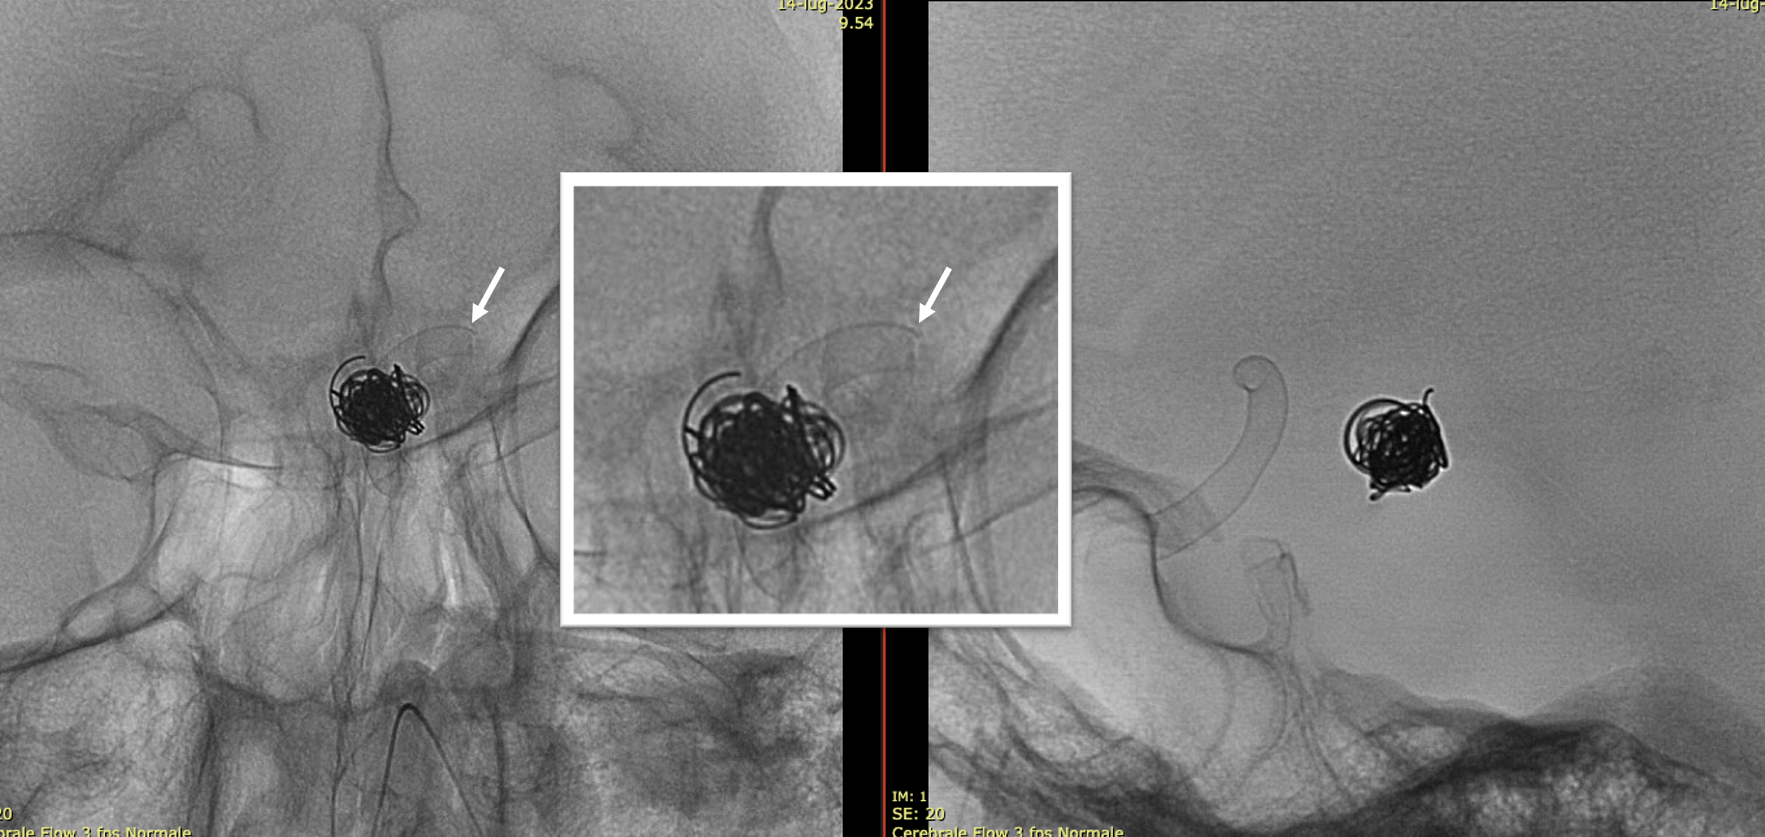

Wide neck MCA trifurcation aneurysm.

Y stenting with Atlas and Lvis Evo, in emergency. The Atlas diameter was too large because of the temporary limited availability in our centre; we can clearly see the struts of the Atlas too open at the level of the aneurysm neck (arrow). Even the microcatheter for coiling is fully visible jailed by the Lvis Evo in M1

The injection of contrast medium (250 mg/ml, 50% dilution, manual injection, same reconstruction protocol as previous images) reduces the visibility of the struts — an important point to consider. Not everything is always the same contrast dilution, same injection rate, etc. etc. — you need to know how to vary every parameter to achieve desired results.